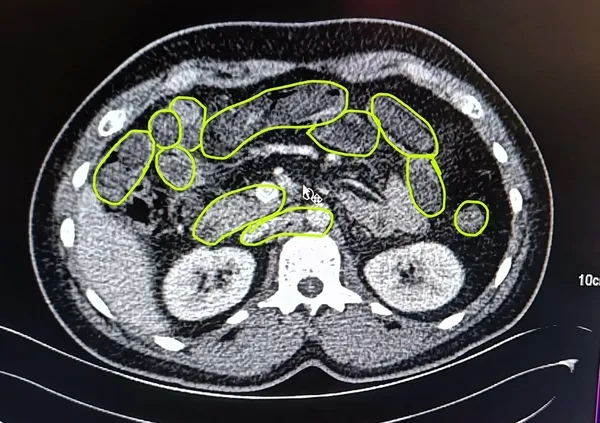

Jandarma daha sonra şüphelileri iç beden muayenesi için Kayseri Şehir Hastanesi’ne götürdü. Burada yapılan görüntülemelerde 3 şüphelinin mide ve bağırsaklarında çok miktarda kapsül şeklinde uyuşturucu olduğu tespit edildi. Şüpheliler, vücutlarındaki uyuşturucunun doğal yollardan çıkarılması için müşahede altına alındı.